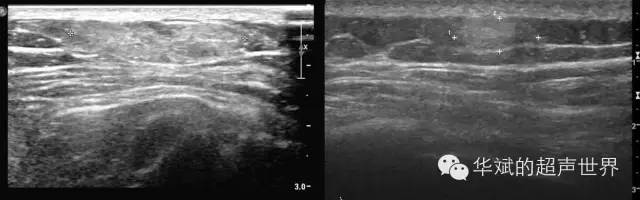

血管脂肪瘤内合并分布有脂肪组织和小血管,一般发生于皮下。通常有包膜。 好发部位:上肢(58%)、下肢(26%)和躯干(16%)。相比于皮下单纯性脂肪瘤,血管脂肪瘤的回声更强、内部回声的异质性更明显。血管脂肪瘤的侧边边界不如单纯性脂肪瘤清晰。更容易谈及内部血流信号。不过多数情况下,仅靠声像图是无法将血管脂肪瘤和单纯性脂肪瘤鉴别开的。

图2 两例皮下血管脂肪瘤。